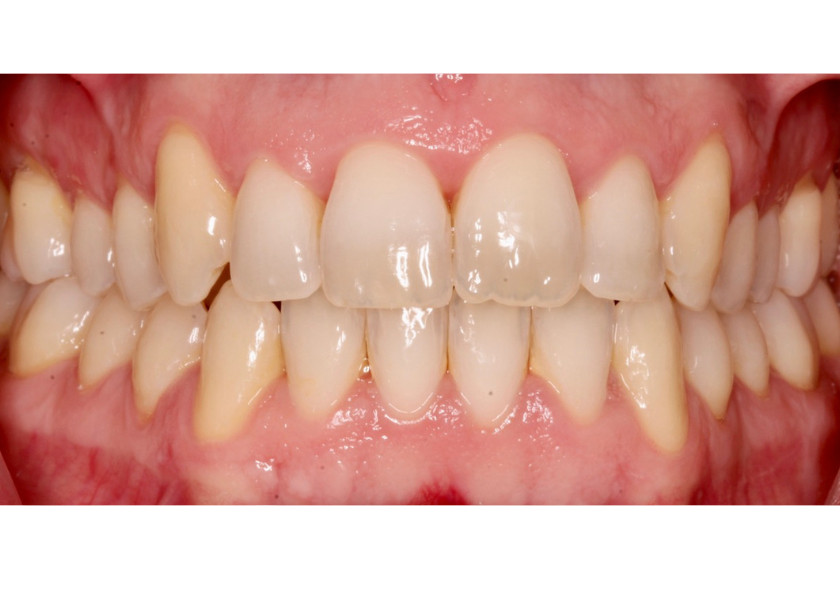

Este paciente acudió a Clínica Dental Urumea para mejorar la estética de su sonrisa. Primero se realizó un tratamiento de ortodoncia con alineadores transparentes Invisalign, para alinear y corregir la mordida cruzada.

Posteriormente, se realizaron blanqueamientos ambulatorios para mejorar

En este caso se ha optado por alineadores Vivera como método de retención.